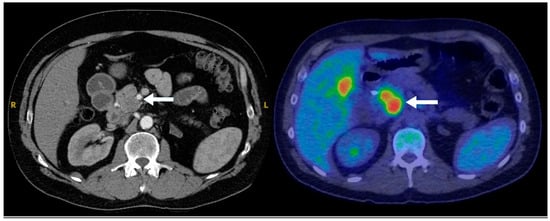

Most cases of hypoenhancing PNENs (n = 11) presented symptomatically (64%), and the lesions were significantly larger (median size 4.8 cm vs. 1.7 cm for typical PNENs). Calcifications were observed in 9% of hypoenhancing PNENs. As pointed out, these tumors were significantly more likely to present with advanced disease compared to other PNEN subtypes (Fisher’s exact test, p = 0.016) (Figure 6 and Figure 7).

Figure 6. A 47-year-old male presenting with biliary obstruction. CT (left): Arterial phase imaging shows a 2.5 cm hypodense mass in the pancreatic head (arrow). PET-CT (right): Performed after ERCP and biliary stent placement, demonstrating an intensely FDG-avid pancreatic head mass (arrow), consistent with a poorly differentiated primary neuroendocrine tumor. Metastatic disease involving porta hepatis and peripancreatic lymph nodes, as well as liver metastases, is also evident on the PET.